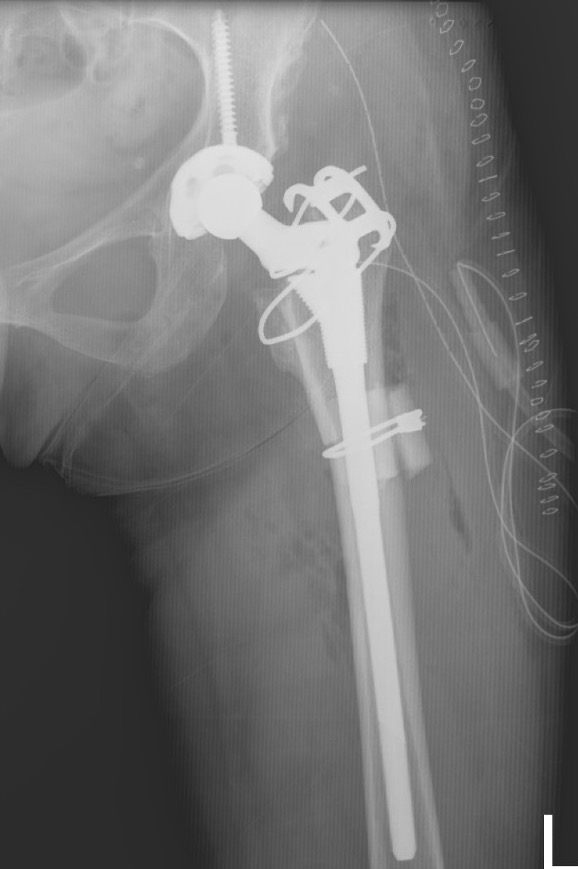

Femoral shortening / Subtrochanteric osteotomy

Technique

Vumedi subtrochanteric osteotomy for Crowe IV

Options

- transverse / oblique / chevron / step cuts

Wang et al J Arthroplasty 2017

- 76 Crowe IV THA

- transverse osteotomy with uncemented stem

- 1/76 nonunion

- 1 acetabulum and 1 femoral stem revised at mean 10 years